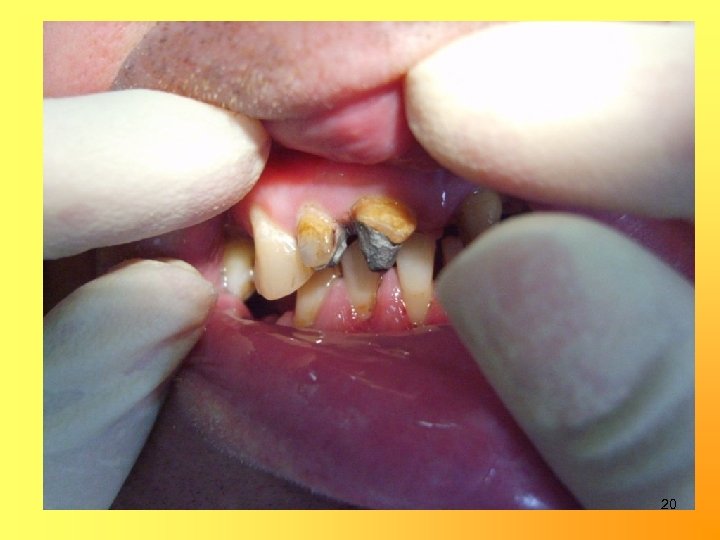

Изготовление культевой штифтовой вкладки: на корни 11, 12 19

20

21